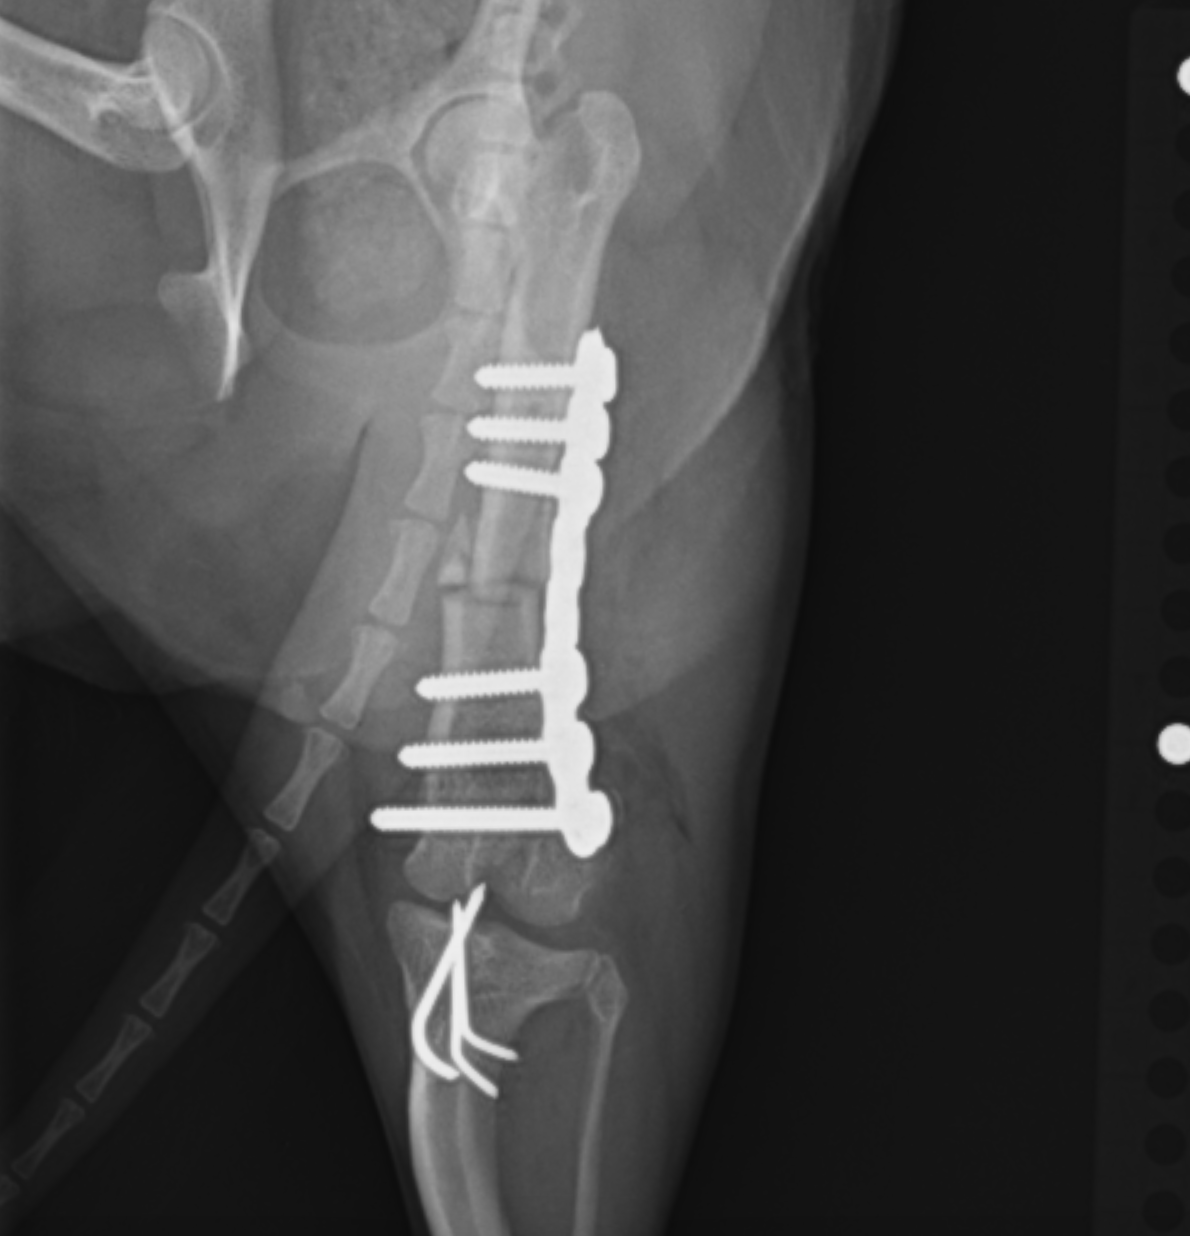

にプラスして大腿骨の矯正骨切術を追加する場合があります。パテラの脱臼に大腿骨の湾曲変形が大きく関わっているからです。この術式の場合には骨の一部を楔形に切断し、プレートで再度固定するという術式を実施します。

大腿骨矯正骨切術:切断した骨と骨をプレートを用いて固定します。術前よりも湾曲が直線に近くなっているのがわかると思います。

ラテラルスーチャー法(Flo法):脛骨の一部に穴を開け、そこに糸を通し、大腿骨の種子骨というところと締結することで、脛骨の内旋を制御し、パテラを脱臼させないようにする方法です。